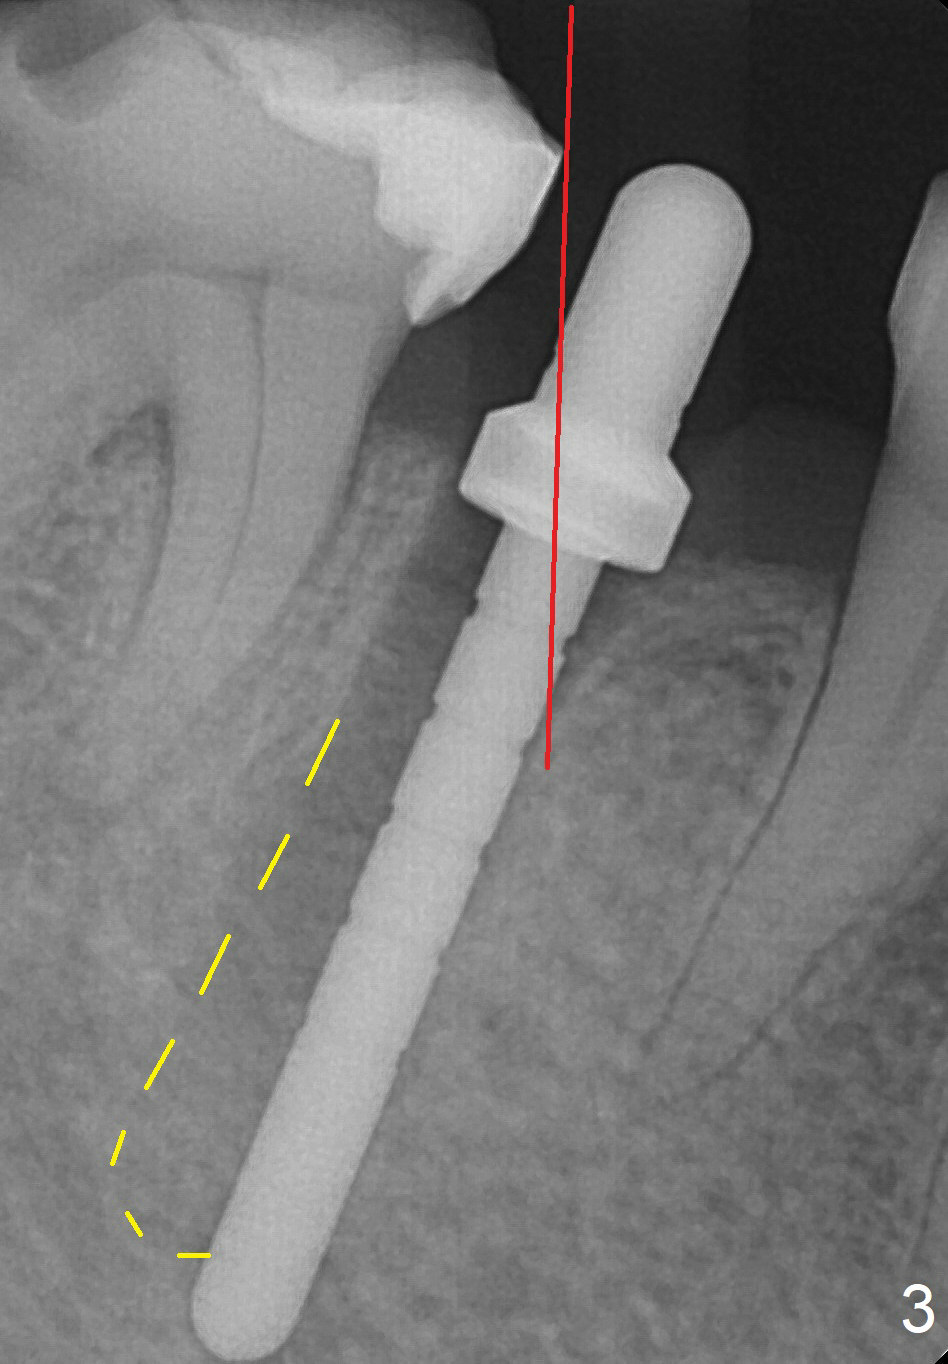

A 67-year-old woman fractures the tooth #29 three months post RCT. There is persistent periapical radio-lucency (Fig.1 yellow dashed line), which is close to the Mental Loop (red dashed line). Since the root of the affected tooth deviates distal, osteotomy will be established mesial (Fig.2). In fact it is not so easily accomplished; the osteotomy is initiated as mesial as possible (Fig.3 (yellow dashed line: original socket)). When a 3.8x16 mm implant is being placed, it is distal (Fig.4). The MO composite of the tooth #30 has to be trimmed for fabrication of an immediate provisional (Fig.5 <).

To place the implant mesially, the initial osteotomy should be established higher in the mesial slope of the socket (Fig.3 red line). Once the drill penetrates the lamina dura (Fig.5 short black line), change the trajectory (Fig.5 red line). A potential drawback may be loss of primary stability when osteotomy increases.

To reduce the chance to injury the buccally located loop, the osteotomy should be as lingual as possible. Initial depth is 19 mm (gingival level, Fig.3). In fact all of the three intraop PAs (Fig.3-5) do not show the Mental Loop until panoramic X-ray is taken immediately postop (Fig.6). There is no postop paresthesia. There appears no gap around the implant 3.5 months postop (Fig.7 >).